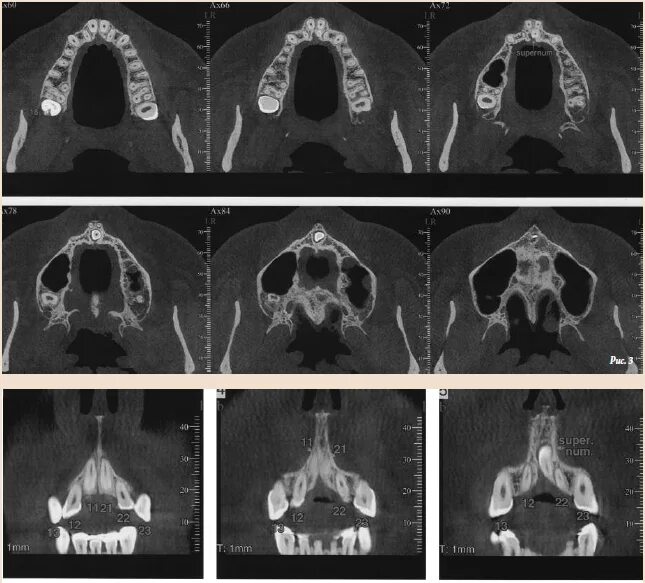

Гипоплазия 12 пары ребер